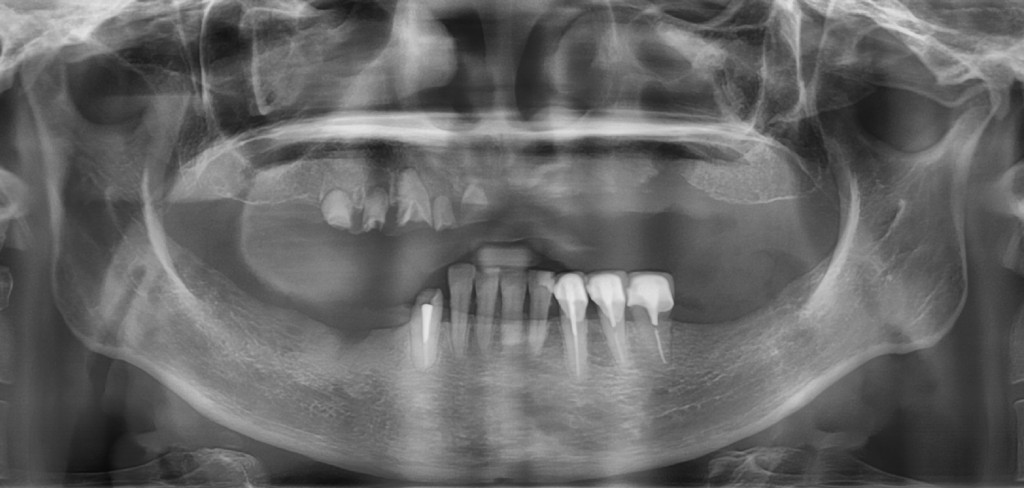

全口重建是我們的專長,針對全口缺牙或是全口鑲牙,需要全面整理,我們有一整套完整的診療模式。

這是因為植牙全口重建不僅是植牙而已,而是牽涉顳顎關節神經及咬肌,訓練咬合排利假牙位置,需要有經驗專業的假牙醫師,做全面綜合的考量,按步就班、細心每個步驟,才能完成令人滿意的植牙醫療成果,我們日出全植牙累積多年醫院全口重建的經驗。

從建的方式有很多種,有固定的、有活動的,有種4顆、有種6~16顆。假牙有些有牙齦有些沒有,有分段式有全口。

植牙假牙泡在口水裡,每天使用是每次承受咬合力挑戰,加上口內細菌繁多,每個人體質不同,牙肉骨頭萎縮,所以全口植牙的長期照護維修尤為重要。不僅在計畫之初就要想到日後可能產生的問題、解決方法、維修的便利性。